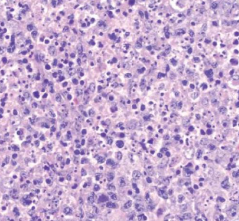

- starry sky pattern

- 星星:macrophages

- 夜空:核濃染的lymphoid cells其中的macrophage,其細胞質內含有apoptotic bodies

- 代表是high grade的lymphoma

- 兒童、年輕人

Burkitt lymphoma

- starry sky pattern